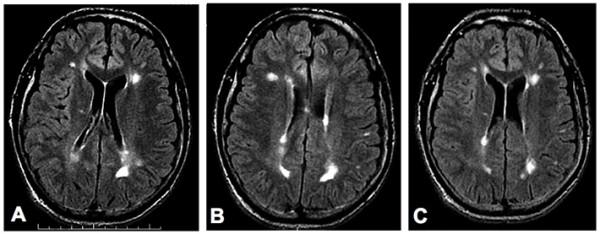

The stromal vascular fraction (SVF) of adipose tissue is known to contain mesenchymal stem cells (MSC), T regulatory cells, endothelial precursor cells, preadipocytes, as well as anti-inflammatory M2 macrophages. Safety of autologous adipose tissue implantation is supported by extensive use of this procedure in cosmetic surgery, as well as by ongoing studies using in vitro expanded adipose derived MSC. Equine and canine studies demonstrating anti-inflammatory and regenerative effects of non-expanded SVF cells have yielded promising results. Although non-expanded SVF cells have been used successfully in accelerating healing of Crohn's fistulas, to our knowledge clinical use of these cells for systemic immune modulation has not been reported. In this communication we discuss the rationale for use of autologous SVF in treatment of multiple sclerosis and describe our experiences with three patients. Based on this rationale and initial experiences, we propose controlled trials of autologous SVF in various inflammatory conditions.

已知脂肪组织的基质血管成分(SVF)包含间充质干细胞(MSC)、调节性T细胞、内皮祖细胞、前脂肪细胞以及抗炎性M2巨噬细胞。自体脂肪组织植入的安全性得到了该手术在整形手术中的广泛应用以及使用体外扩增的脂肪来源MSC的正在进行的研究所支持。马和犬的研究表明未扩增的SVF细胞具有抗炎和再生作用,已产生了有前景的结果。尽管未扩增的SVF细胞已成功用于加速克罗恩瘘管的愈合,但据我们所知,尚未有关于这些细胞用于全身免疫调节的临床应用报道。在本交流中,我们讨论了使用自体SVF治疗多发性硬化症的基本原理,并描述了我们对三名患者的经验。基于这一基本原理和初步经验,我们提议对自体SVF在各种炎症性疾病中的应用进行对照试验。